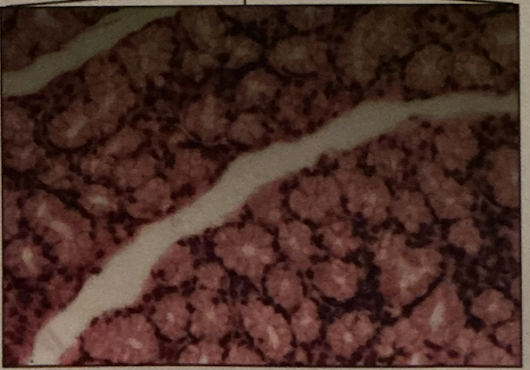

liver

bile duct

hepatocytes

cells that make/secrete blood proteins, store glycogen, release glucose, catabolize drugs & breakdown metabolic products

bile acids

created & —> gallbladder for storage and release; mediate fat digestion

cirrhosis

cirrhosis

disease marked by fibrous fatty deposits in fiber

pancreas

pancreas

endo & exocrine; exocrine synthesizes & secretes enzymes to digest food & bicarbonate that neutralize chyme

islet of langerhans

small endo clusters that are mix of cell types

alpha cells

secrete glucagon - stimulate liver to depolymerize glucose from glycogen & secrete glucose

beta cells

secrete insulin - stimulate tissue to take up glucose